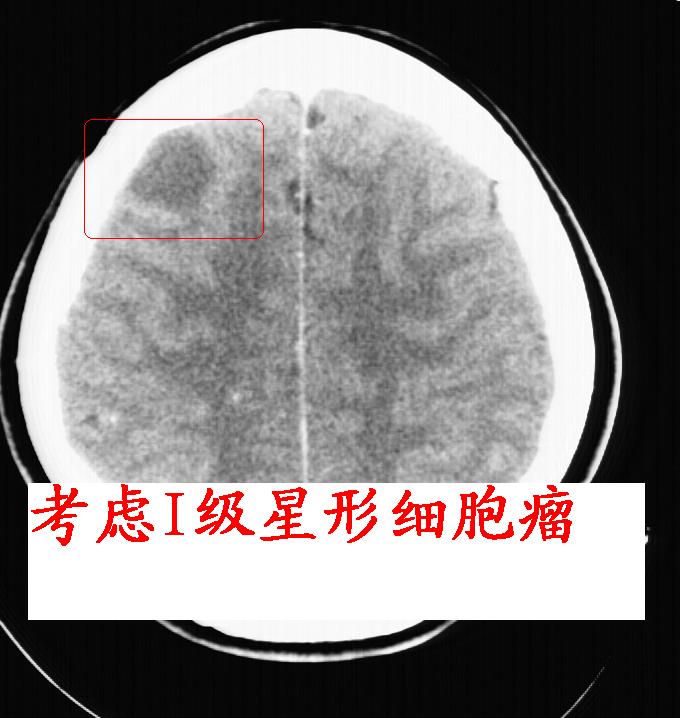

考虑 1 低级星型胶质细胞瘤 2 蛛网膜囊肿

1级星型细胞瘤的可能性大.

水肿及强化不明显,考虑低分级胶质细胞瘤可能性大

水肿及强化都不明显!也没见钙化影!考虑i级星型细胞瘤可能性大!

强化后呈环状强化,支持1级星型细胞瘤可能.

右额叶低密度灶,脑回分离,无水肿及强化,考虑脑脓肿,建议mri检查

右顶叶靠近脑表面圆形低密度灶,周围无水肿及占位效应,增强病灶无明显强化,考虑:右顶叶低分级星型细胞瘤。

右额叶上部皮质区见类圆形低密度区,边界不清,无强化,无钙化。

支持大多数战友的意见,1级星形细胞瘤。